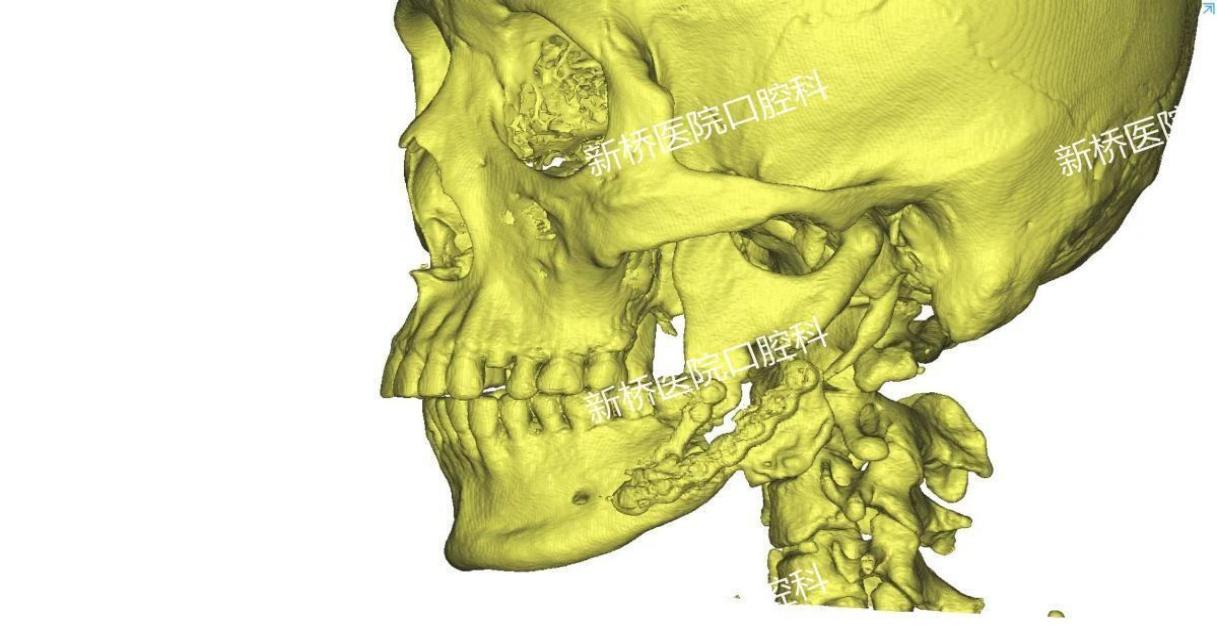

诱导膜技术修复颌骨缺损

多是在骨科当中应用,用于处理骨折、关节病变或骨质疏松等问题。它的主要原理就是在植入之后,能形成一层诱导膜,这层膜内部可以产生成骨微环境,诱导成骨,膜内填入骨松质后就可以在它的诱导下形成新骨。因此骨水泥主要有填充缺损、支撑以及诱导成骨的作用。